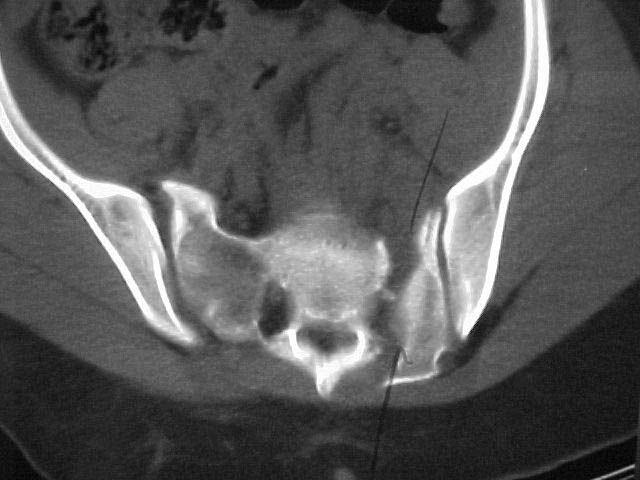

A 17 year old female involved in a car crash. Has a Type III lateral compression injury to her pelvic ring using the Young-Burgess classification. A windswept pelvis if you will. The images are included. There appears to be posterior displacement of the left hemipelvis as well.

Fx/Injury Evaluation:

Impression: unstable, requires reduction with stabilization, will continue with continued deformity if not stabilized

Thanks for submitting your case to the forum, I am sure you will soon be toxic with recommendations that you will have to filter through. I would like to offer some rather elementary advice: Your patient needs to have appropriate inlet and outlet films adjusted for her anatomy;i.e.,she appears to be somewhat lordotic and that would require the gantry angle to be adjusted with each view. The same would be true for the CT scan it appears as though the angle of the gantry is tangential to the slope of the sacrum (sacro-horizontal line if you will) and that gives a distorted view of the posterior ring injury.